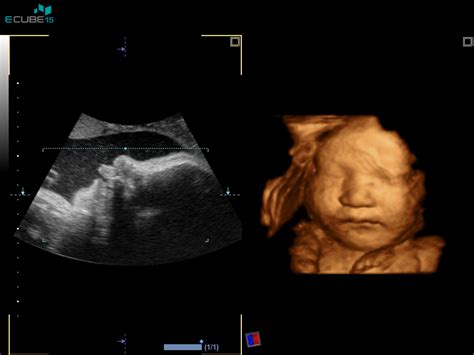

V primeru medenične vstave je ena od možnosti, ki jo ponujajo zdravstvene ustanove, zunanji obrat ploda. Ta postopek običajno izvajajo med 36. in 37. tednom nosečnosti, ko se zdravnik s pomočjo ultrazvoka prepriča o legi otroka, količini plodovnice, velikosti plodove glavice in materine medenice. Cilj je, da ginekolog z rokami obrne plod v glavično lego. Uspešnost zunanjega obrata je približno 50-odstotna. V Sloveniji zunanje obrate izvajajo v nekaterih porodnišnicah, kot sta Ljubljana in Kranj, medtem ko v drugih, na primer v Novem mestu, nosečnico napotijo drugam.